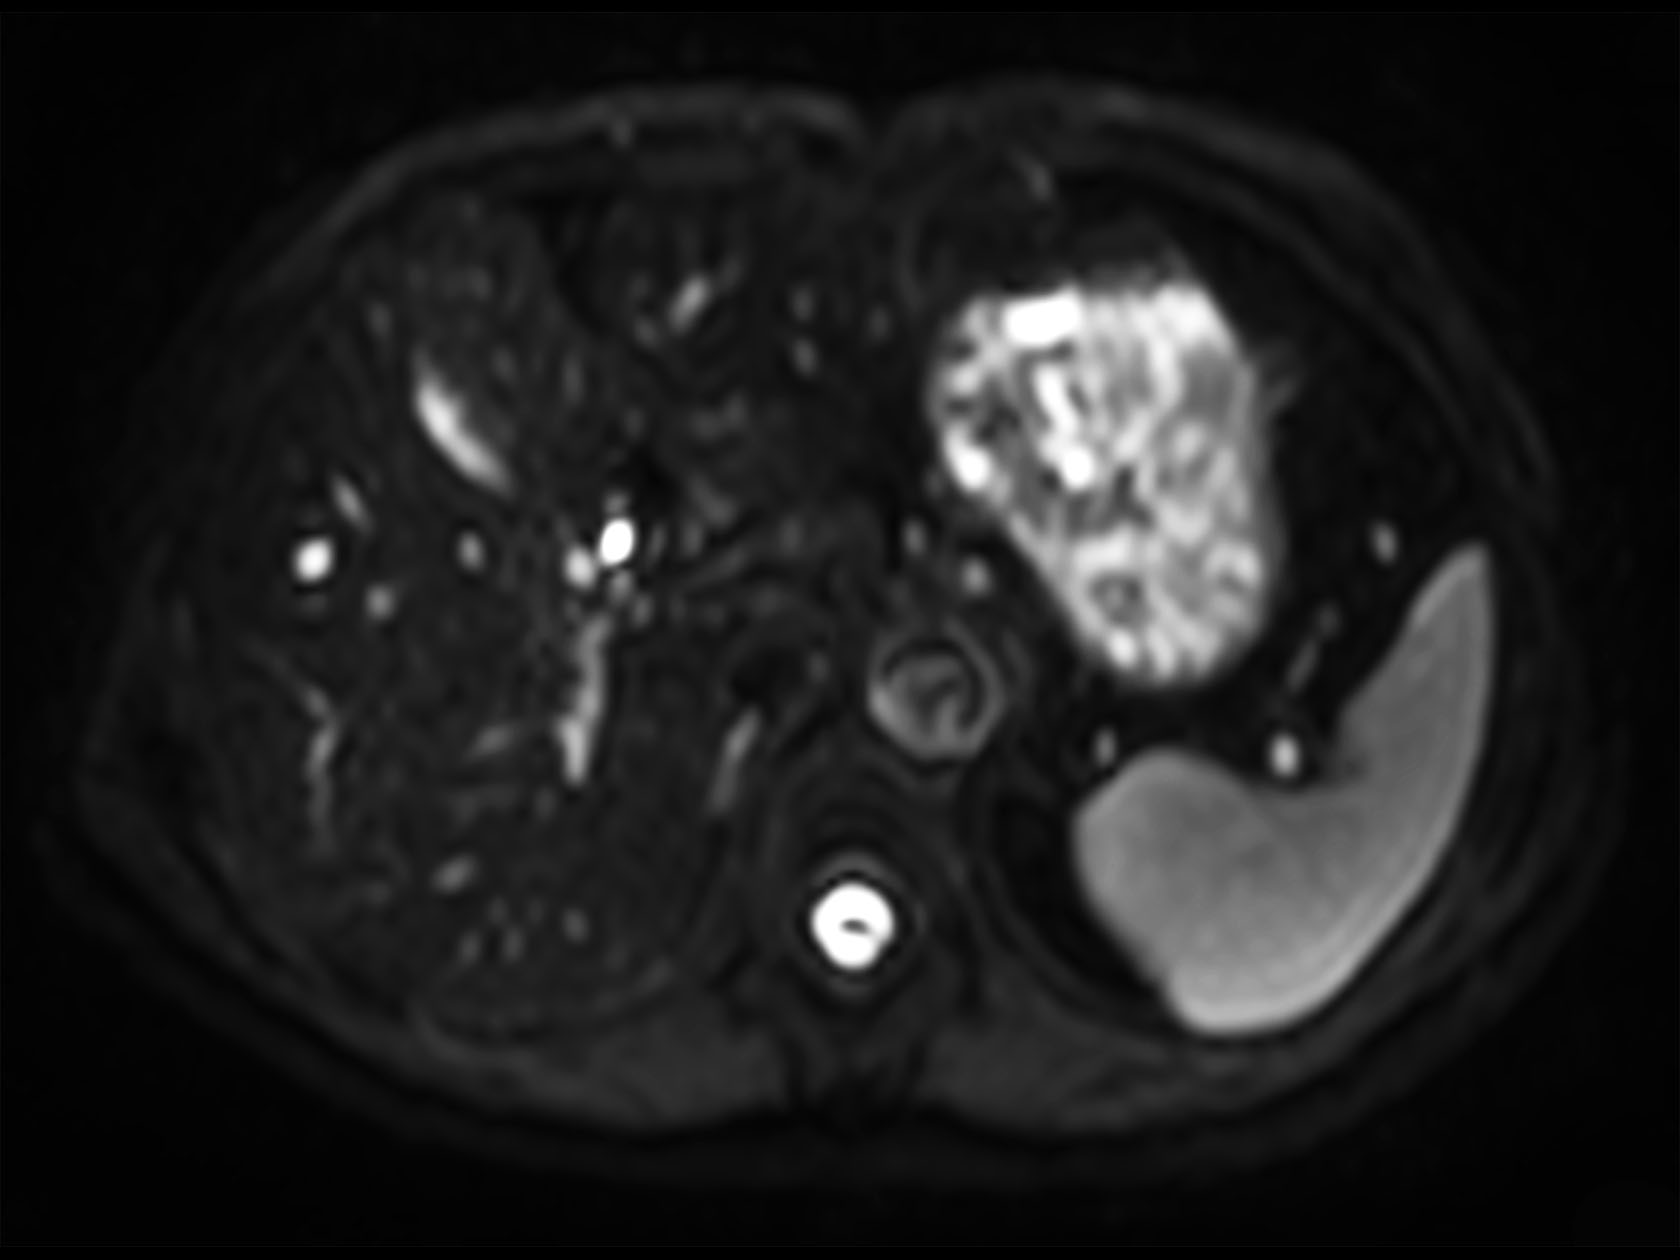

Diffusion (b1000)